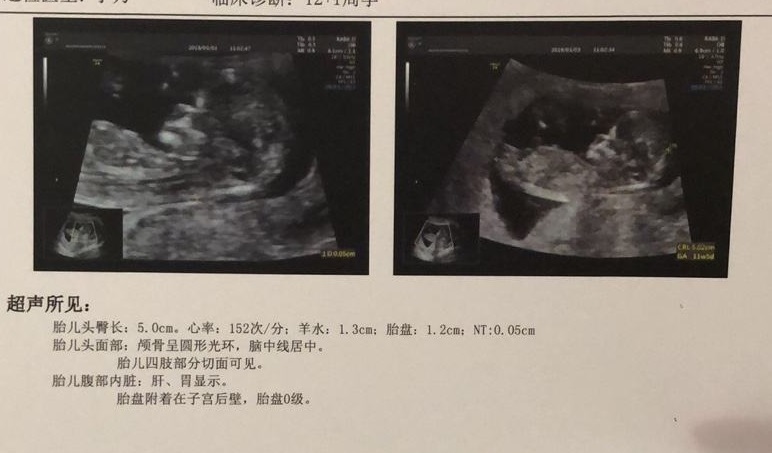

多囊外加睪酮高,12月-4月懷孕歷程我來詳細講述

12.20,今天最後一粒達英吃完,目前胸漲的感覺仍然有,中藥又開了一個星期的,已經慢慢適應了。雖然很難吃,但是我需要堅持。準備明天去人民查睪酮,老天保佑,希望能降下來點,讓我有信心。多囊促排的一些碎碎念12.22,今天早晨到醫院先抽了血,單子上讓三天後取。正好這幾天過敏了,沒著急走,查了查過敏的問題,開了藥,打了針,到了十一點多,正好吃飯的時間。於是在醫院附近找了個飯館,吃飯當中,簡訊提示我,化驗...